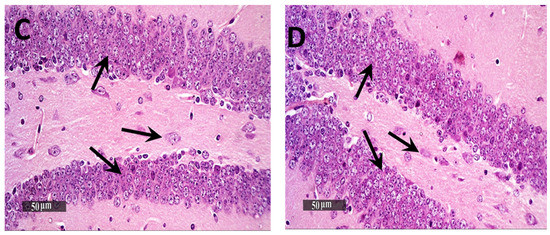

Light Microscopic examination of the hippocampal subregion in normal control samples demonstrated normal morphological features of hippocampal CA3 and dentate gyrus regions. The CA3 subregion showed well organized cellular elements, including 5–6 cells thick pyramidal neurons middle layer with apparent intact subcellular details (Figure 5A—black arrows) (mean intact pyramidal neurons count in Toluidine blue-stained sections = 65 cells/field) (Figure 6A). Intact neuropil with normally distributed glial cells and normal vasculatures were observed. However, the AD-induced model samples CA3 subregion showed severe neuronal damage with abundant records of degenerated, hypereosinophilic and shrunken neurons losing their subcellular details (Figure 5B—Red arrows) accompanied with moderate perineuronal oedema and higher records of astrogliosis as well as microglial cells infiltrates (Figure 5B—arrowhead). The mean intact neurons count was 12 cells/field in Toluidine blue-stained tissue sections (Figure 6B). Gp 3 samples demonstrated significant neuroprotective efficacy with many apparent intact neurons (Figure 5C—black arrows) and few sporadic neuronal degenerative changes records (Figure 5C—Red arrows) with mean intact neurons count = 50 cells/field in Toluidine blue-stained tissue sections (Figure 6C). Mild persistence records of astrogliosis or microglial cell infiltrate were shown. Moreover, Gp 4 samples showed well organized morphological features of CA3 regions with almost apparent intact neurons (Figure 5D—black arrows) and minimal records of abnormal glial cells infiltrates or oedema, with mean intact cells count = 61 cells/field respectively in Toluidine blue-stained tissue sections (Figure 6D).

Figure 5.

Neuroprotective histological effect of different treatments on CA3/hippocampal sub-regions of AD model. (A) normal group, (B) negative control group (received 0.9% saline), (C) positive control group (received resveratrol suspension) and (D) test group (received resveratrol bilosomes). H&E stain, 400×.